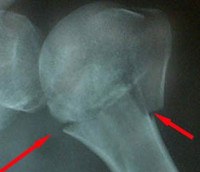

Для уточнения диагноза назначают рентгенографию плечевого сустава в двух проекциях: прямой и «эполетной» (аксиальной). «Эполетный» снимок выполняют, отводя плечо от туловища под углом 30-40 градусов. Большее отведение категорически не рекомендуется, поскольку может усугубить смещение отломков. В сомнительных случаях используют КТ плечевого сустава. При подозрении на сдавление сосудисто-нервного пучка пациентов направляют на консультацию к неврологам или нейрохирургам и сосудистым хирургам.